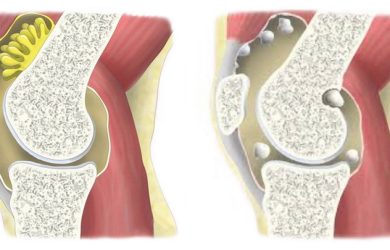

Хондроматоз колінного суглоба - хронічний патологічний процес, при якому синовіальна оболонка суглоба частково зазнає змін, поступово перетворюючись на